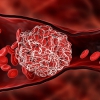

2. Xuất huyết nặng

Do giảm tiểu cầu và rối loạn đông máu.

Xuất huyết dưới da